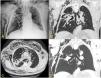

We report the case of a 74-year-old man with lung adenocarcinoma (pT1aN0M0) in the right upper lobe (RUL), treated by segmental resection and post-surgical radiation therapy (RT). Local tumor recurrence was detected during follow-up. Given his high comorbidity, CT-guided microwave thermal ablation (MTA) was administered. The procedure went smoothly and the patient was discharged. However, 1 week later, he attended the emergency room, reporting an oppressive sensation and respiratory distress. On examination, he was eupneic and stable, with crepitation of the soft tissues of the chest and bitonal dysphonia. A chest X-ray revealed marked subcutaneous emphysema, with no signs of pneumothorax (Fig. 1A). Chest CT showed pulmonary cavitation at the MTA site communicating with a bronchus leading to the RUL and with a large gas-filled space in the chest wall, along with extensive pneumomediastinum and subcutaneous emphysema (Fig. 1B–D), findings consistent with bronchial fistula (BF) and bronchocutaneous fistula (BCF) from the post-MTA cavity. The patient was hospitalized and kept under observation and the emphysema was drained. Progress was favorable.

Chest X-ray, PA projection (A). Extensive subcutaneous emphysema in right chest wall and supraclavicular and cervical region, along with pneumomediastinum (arrows). Poorly delimited mass in the right upper lobe (asterisk), apparently communicating with a bronchus leading to that lobe (arrowheads). Chest CT without intravenous contrast medium, pulmonary parenchyma window. Multiplanar reconstructions in coronal (B) and axial (C) planes, with minimum intensity projection (D). The air cavity is clearly seen surrounding the treated mass (arrowheads in B and C), communicating with a bronchial branch to that lobe (arrowheads in D), along with pneumomediastinum (white arrows) and extensive subcutaneous emphysema predominantly in the right chest wall. Note the large gas-filled space in the chest wall adjacent to the post-thermal ablation cavity, suggesting communication between the two cavities (C and D asterisk). There are also signs of centrilobular emphysema predominantly in the upper lobes.